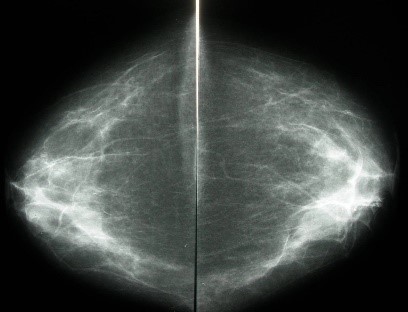

Which of the two standard projections is shown here

Cranio-Caudal

Why are images presented back to back

Images must be mirror images as this aids film reading easier to pick up asymmetric densities